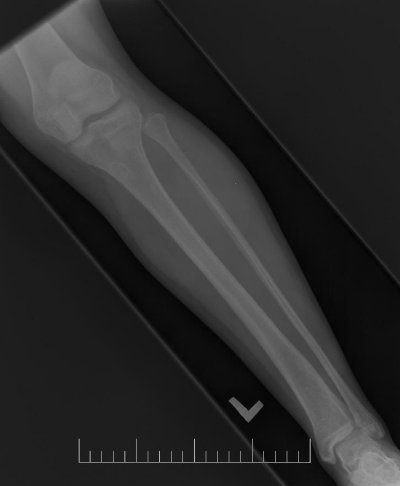

A 10-year-old female presented with left lower leg pain that had progressively increased over the duration of 1 year. On physical examination, tenderness was elicited on palpation of the distal tibia. Routine laboratory testing was normal. X-Ray was performed and revealed a lytic lesion with sclerotic margins in the left lower tibia (Figure 1). MRI was subsequently performed, demonstrating a left lower tibia lesion with low signal intensity on T1 weighted images (Figure 2), and high signal intensity on T2 weighted images (Figure 3). Pathology of the tumor revealed a diagnosis of a CMF. She was treated with curettage and autologous bone grafting (Figure 4). Post op eratively the left leg was immobilized with a plaster cast with restricted weight bearing (Figure 5). Follow up X-ray after 5 years demonstrates no tumor reoccurrence (Figure 6, Figure 7).

Figure 4: Post op lateral X-ray of the left tibia/fibula.

Figure 5: Post op AP X-ray of the left tibia/fibula.